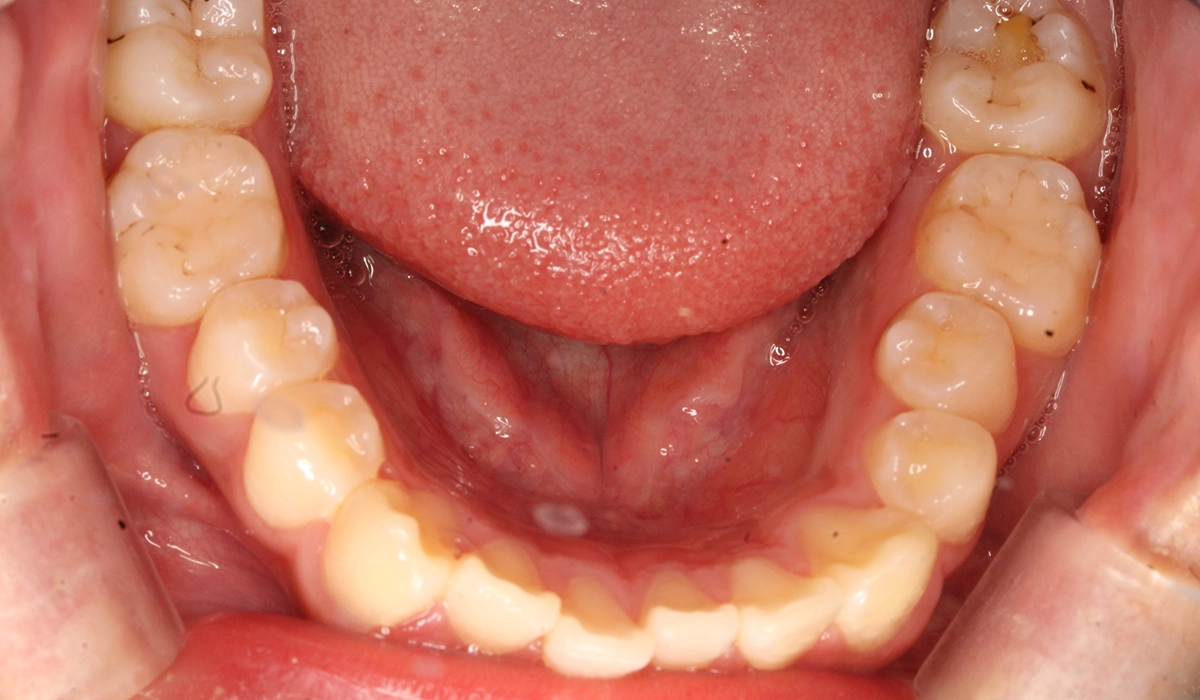

術前:下顎